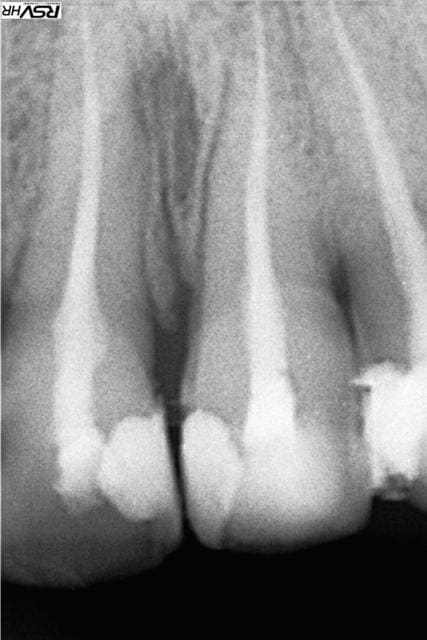

En PJ le dernier specimen, 28 ans, CMU mais dispo que le soir (ben oui il travaille au noir) la bouche en tchernobyl. Je n'ai fait que répondre à sa demande : des dents blanches devant. Pour les extractions allez voir ailleurs.